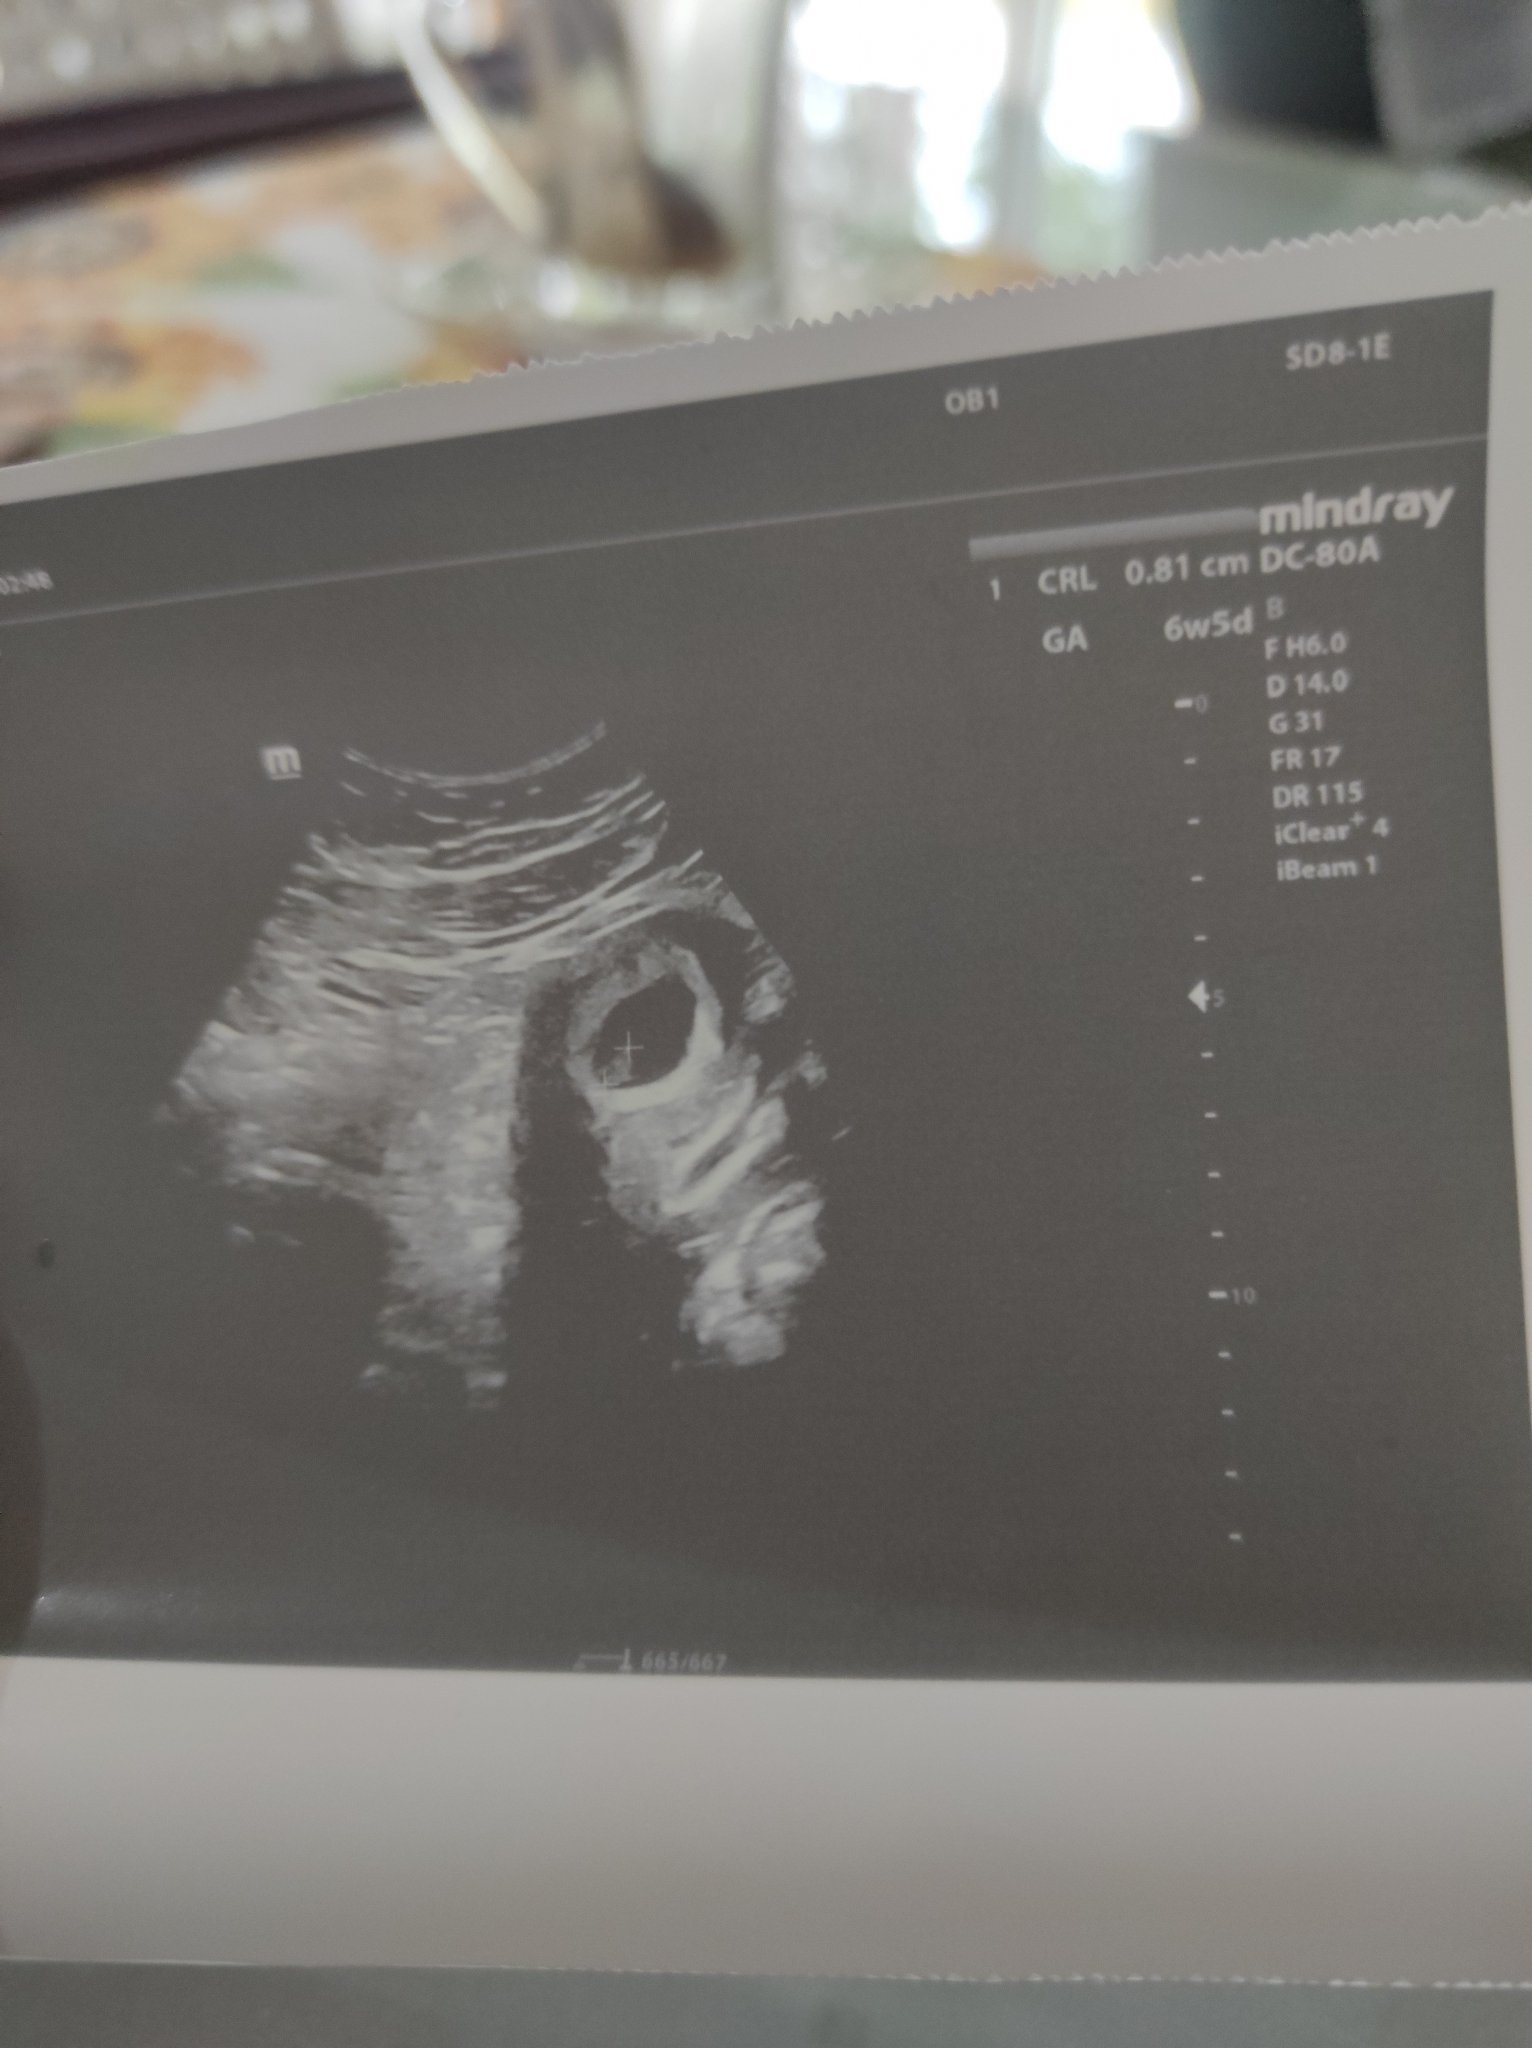

Пише 6 седмици 5 дена.

Гледали са ме само с вагинален ехограф в началото, виждаше се бременност някъде в 5с и 6 дена. Реално в чужбина първите прегледи са чак в 8 седмица, дотогава нито много се вижда, нито нещо може да се направи освен да се чака. Първите месеци се гледа само с вагинален ехограф, през корема не се виждало добре. Това знам.

От снимката можем само да видим , че отговаря на 6 + 5 г.с. Знаете ли , или поне предполагате ли кога ви е била овулацията , щом сте с нередовен цикъл . И колко нередовен е бил ? Доктора изрази ли съмнение в развитието ? И как изчислихте , че влизате във втори месец ?

Лекар трябва тук. Да се види дали става въпрос за изоставане в развитието или забременяване доста по-късно от очакваното с ПРМ 11.07.

Няма такова нещо като "на ръба". Или се развива бременността или не. Лекар трябва да ви прегледа и с ехохраф и да се пуснат кръвни, за да се види как се движи хормона.

Нормално е в ранна бременност да не се види нищо на коремен ехограф, затова в повечето случаи се използва вагинален. Вижда се плоден сак с ембрион на тази снимка, видяха ли сърдечна дейност?